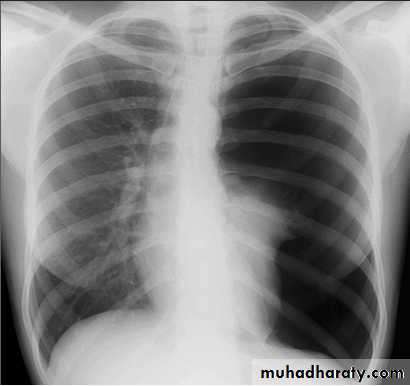

Pleural effusion

X-ray of pleural effusion